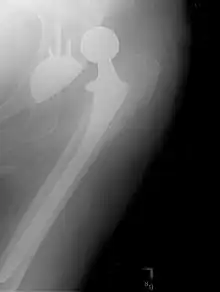

Prothèse totale de hanche

Une prothèse totale de hanche (PTH) est un dispositif articulaire interne qui vise à remplacer l'articulation de la hanche et lui permettre un fonctionnement quasi normal, en tout cas permettant la marche.

La prothèse totale de hanche (PTH) est une intervention chirurgicale dont l’efficacité et la régularité des résultats sont remarquables en assurant

- le soulagement des douleurs ;

- l’amélioration de la fonction ;

- l'amélioration de la qualité de vie.

La longévité de la prothèse dépend de plusieurs facteurs dont les principaux sont le type d’implant, la méthode de fixation, la technique de pose (et donc le chirurgien et son équipe).

Actuellement, les prothèses totales de hanche (PTH) durent entre 15 et 20 ans dans la majorité des cas (environ 90 %). Néanmoins, cette durée varie d'un patient à l'autre. Plusieurs facteurs expliquent cette variation comme l'âge du patient ou son activité (plus la personne est active, moins la durée de vie de la prothèse est importante). De plus, certaines pratiques telles que les sports violents sont fortement déconseillées puisqu'elles contribuent à augmenter l'usure diminuant alors la durée de vie de la prothèse de hanche.